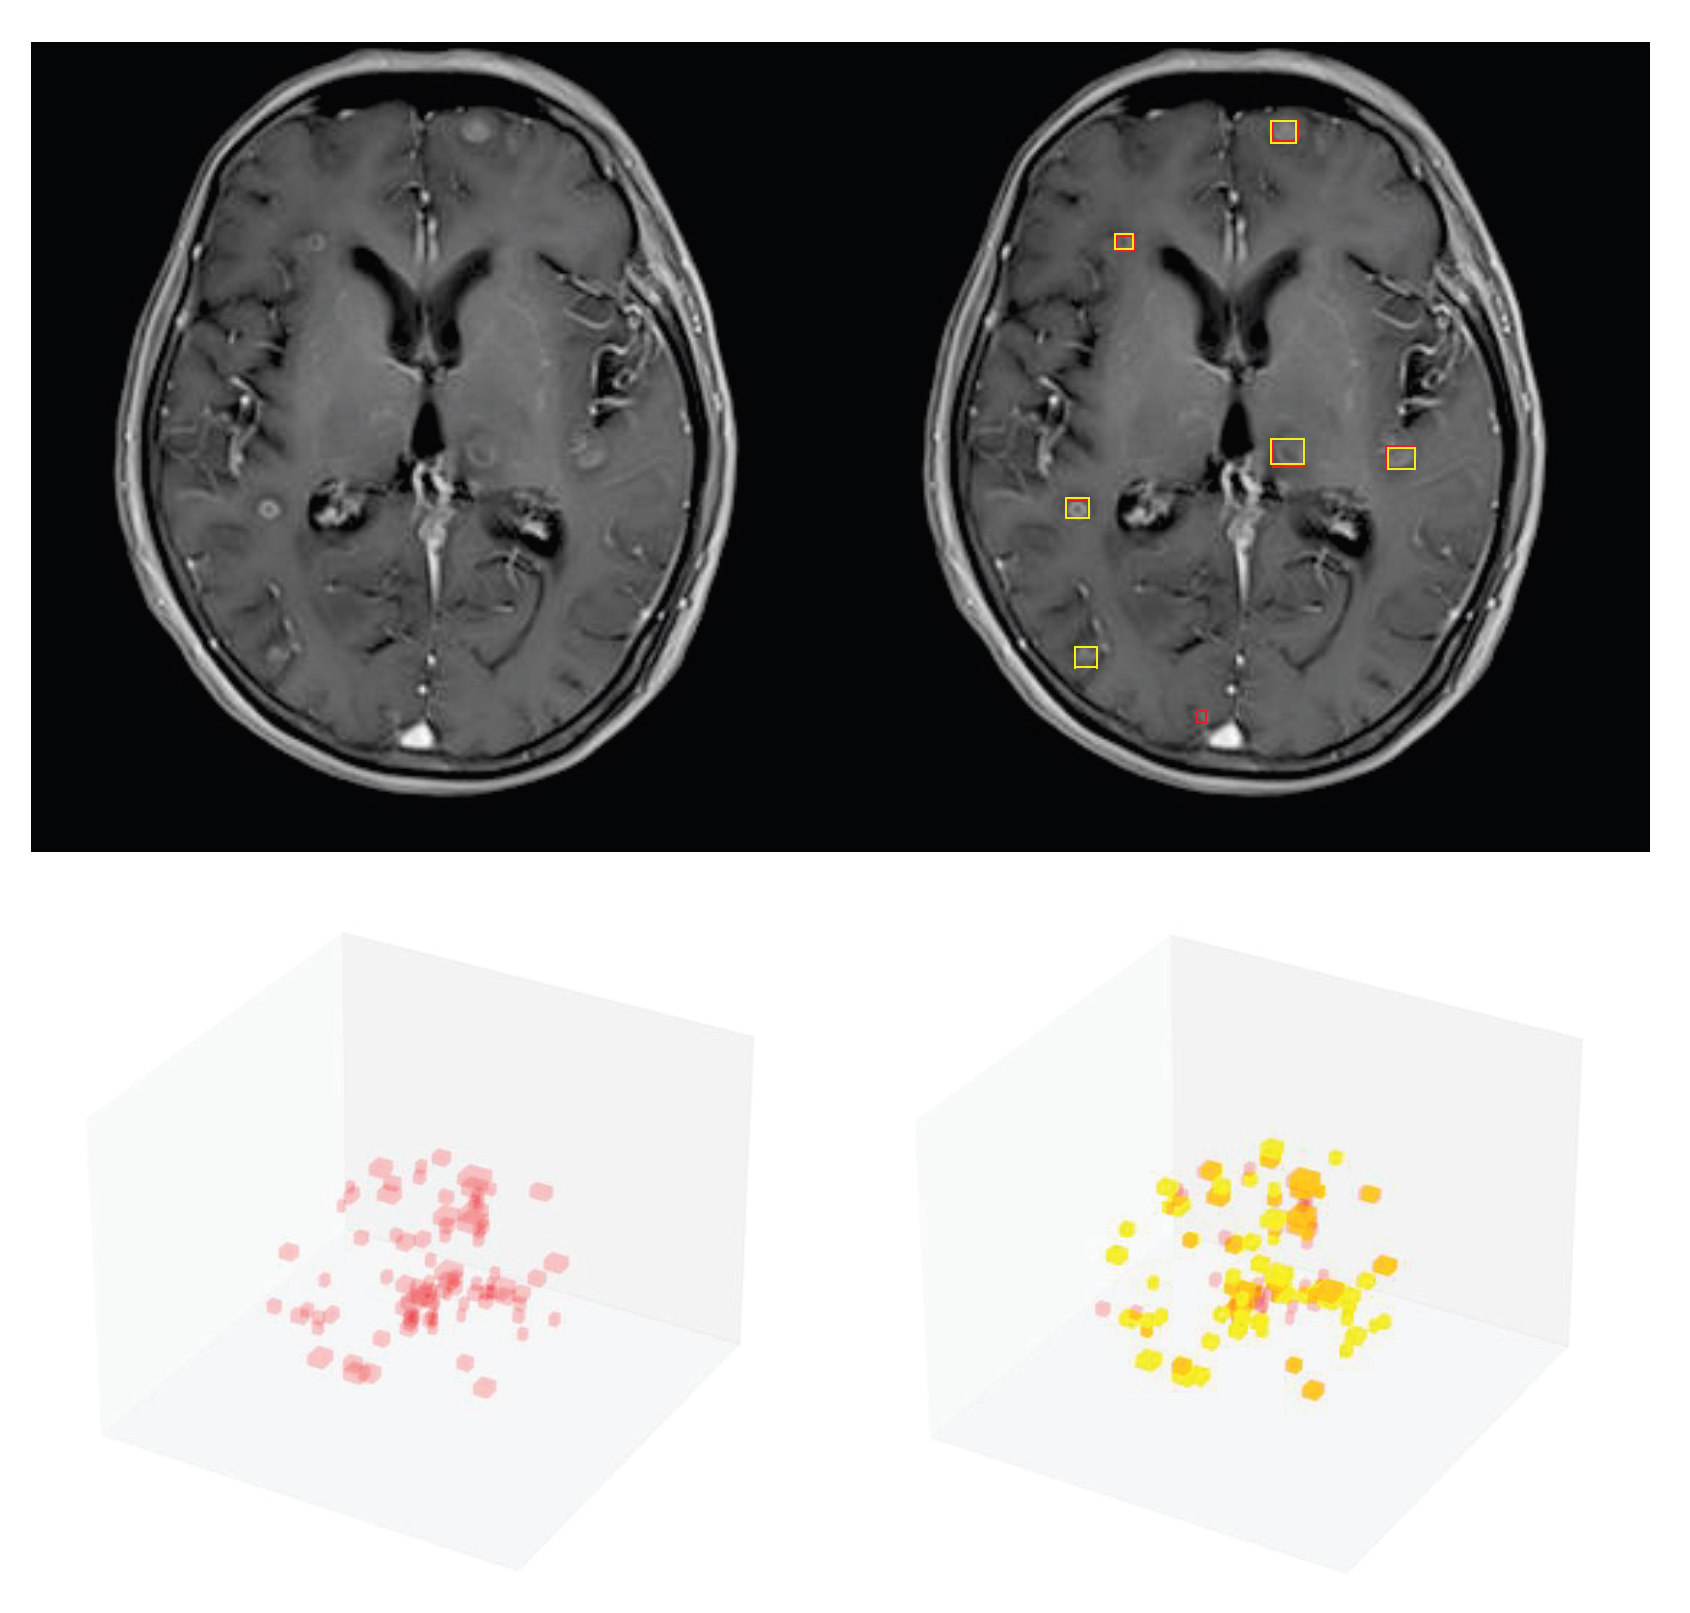

3.1. Detection Performance of SA-YOLOv5

3.4. Detection Performance on the External Testing Set